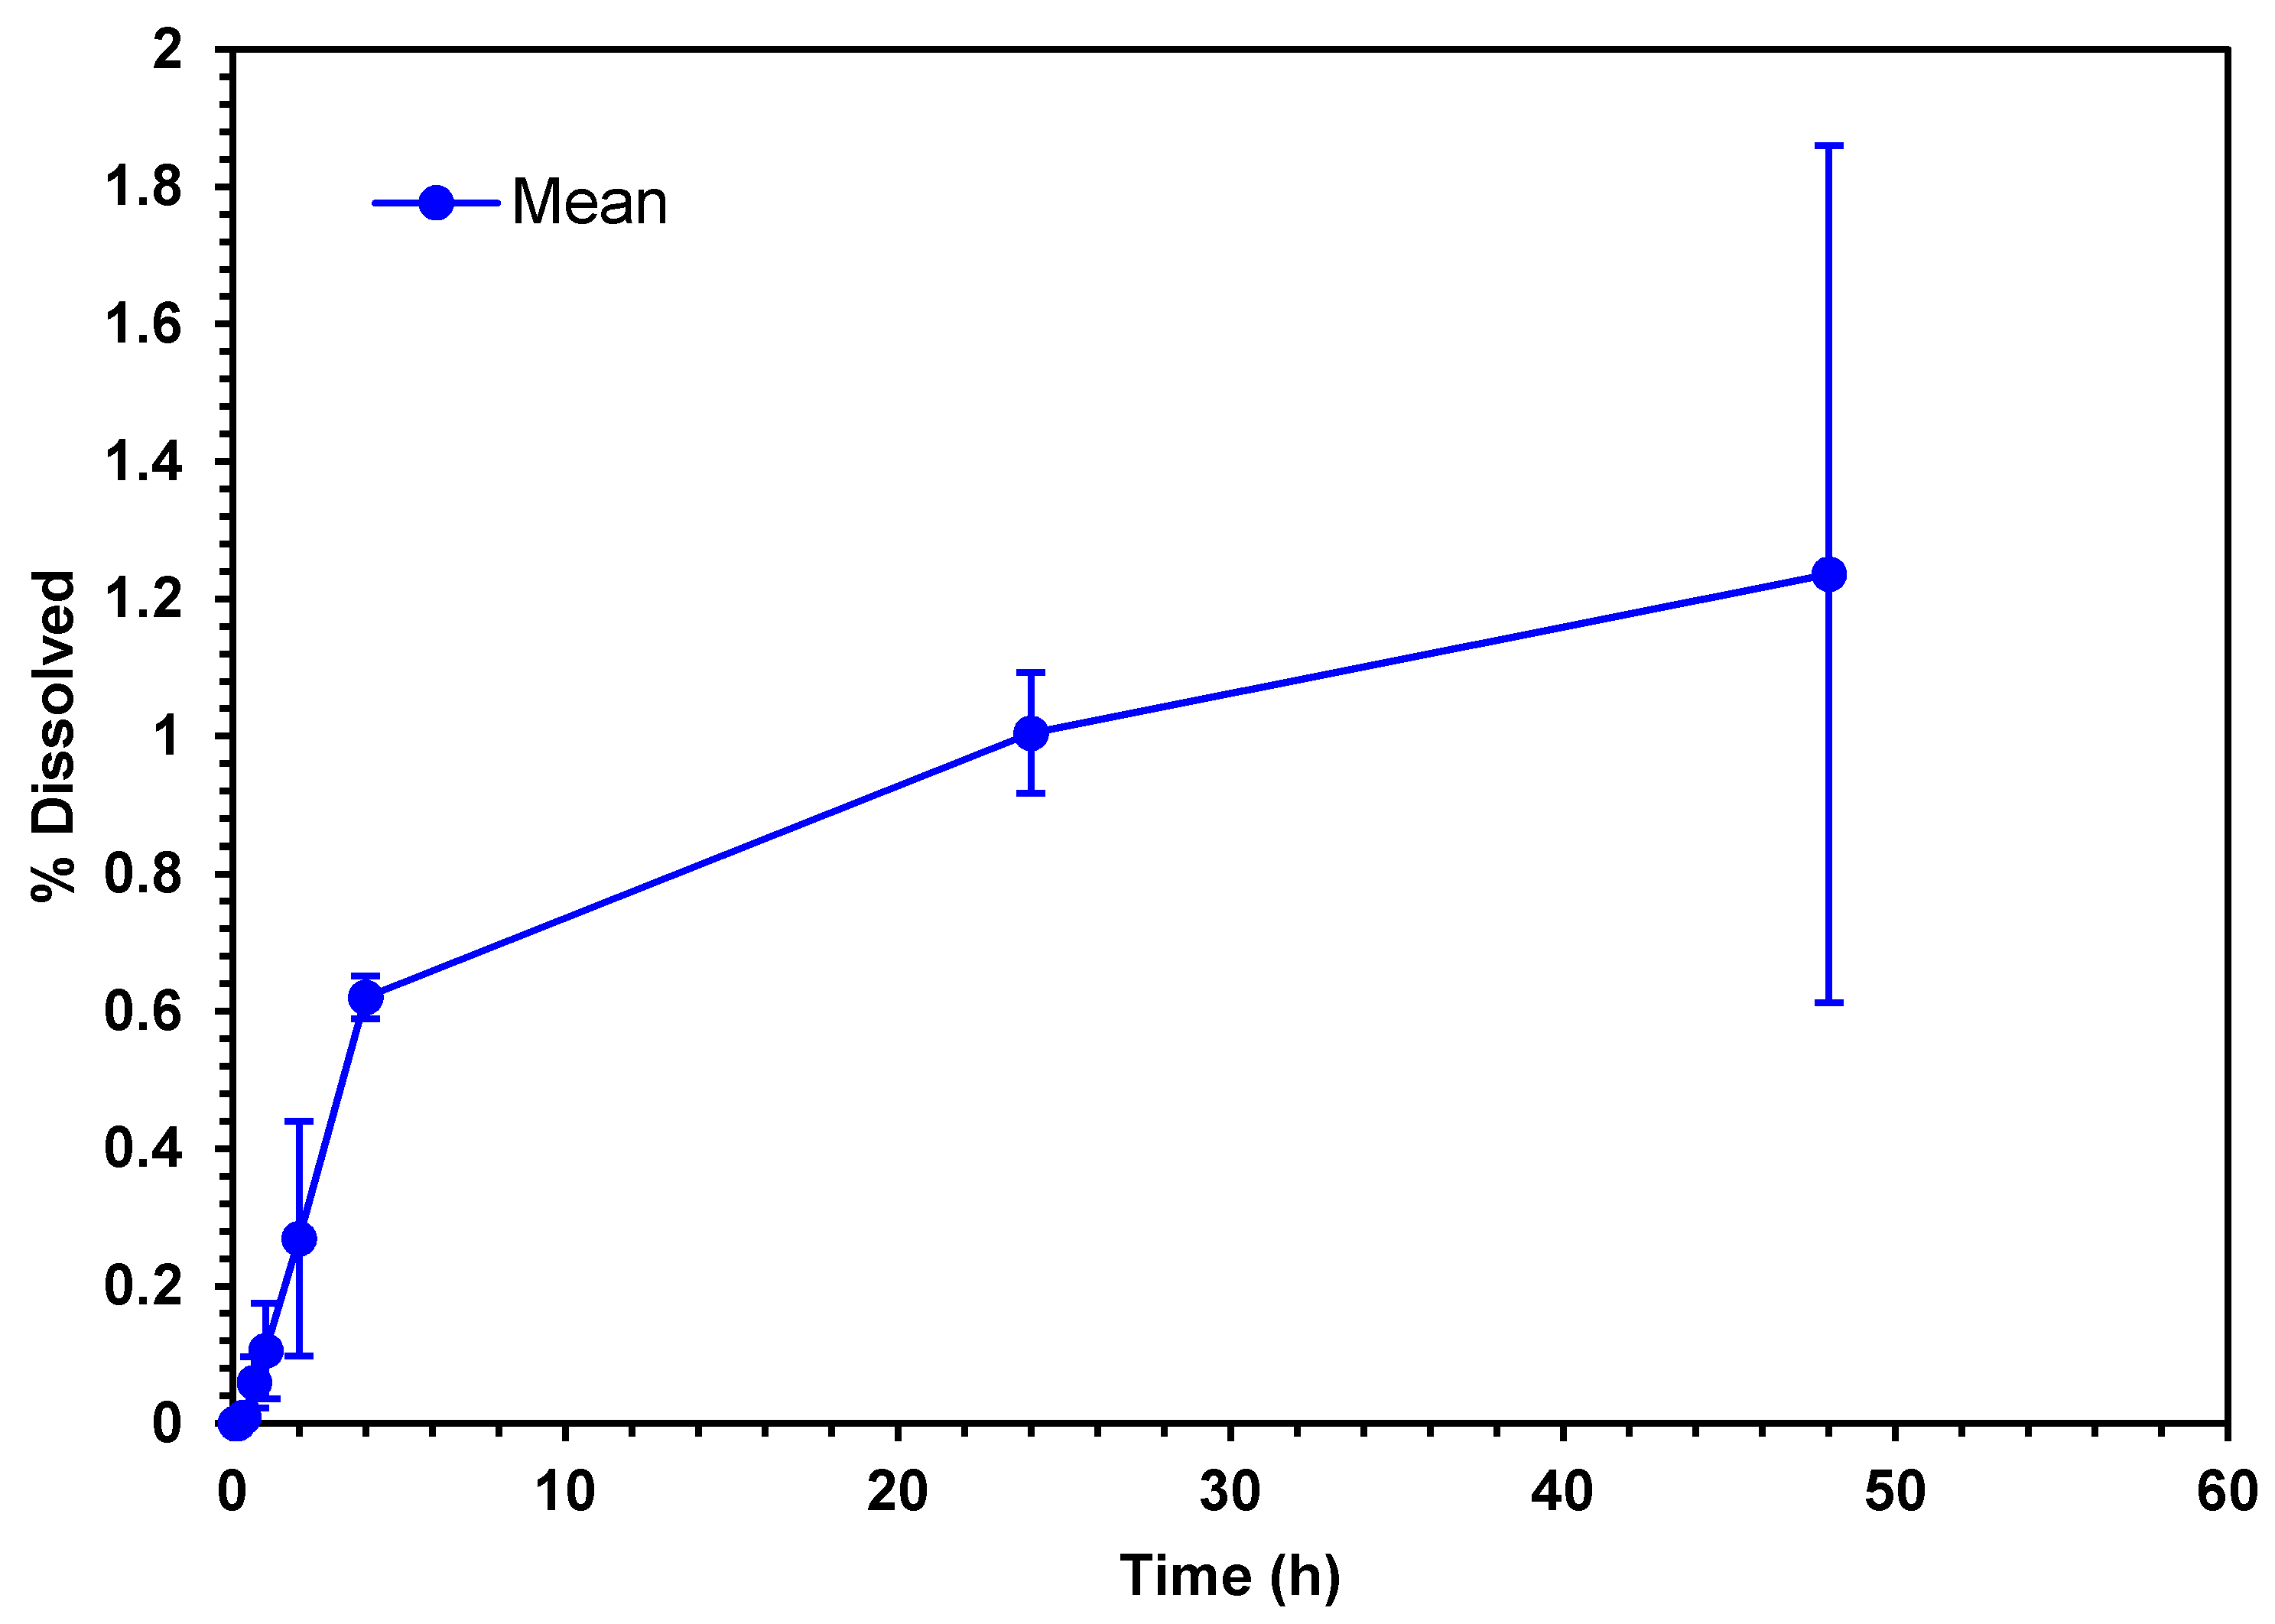

3.1.6. Drug Release Profiles and Kinetic Drug Release